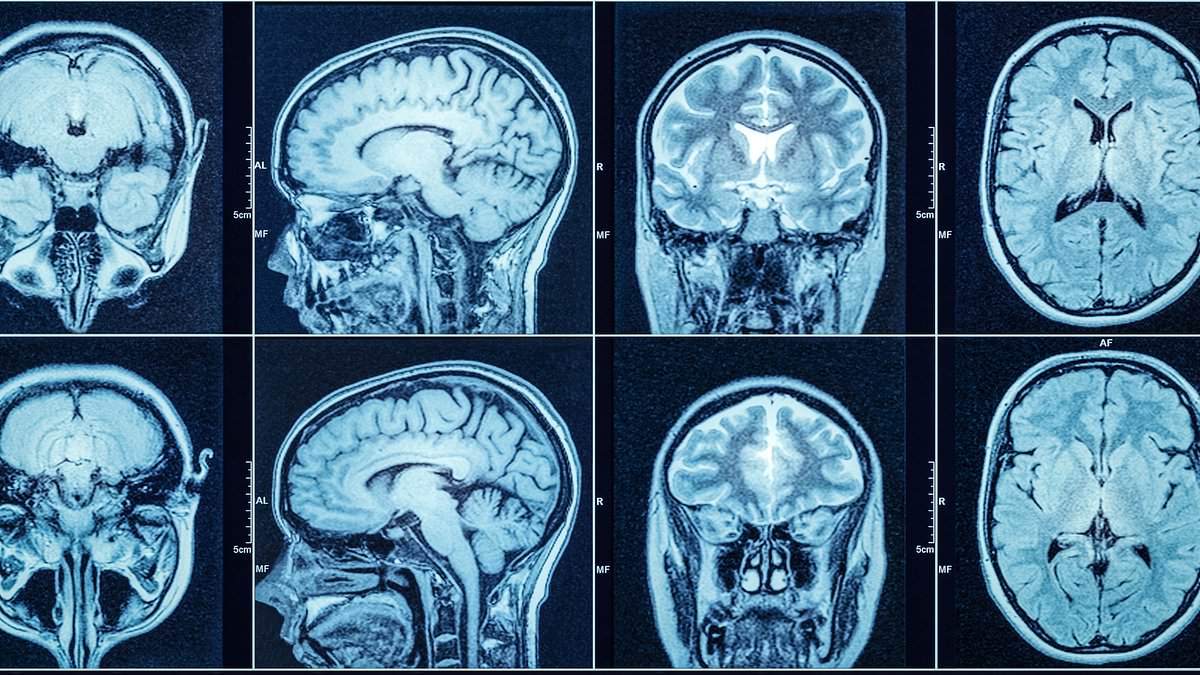

University College London-led trial of AMT-130 shows significant slowing of disease in 29 patients over three years